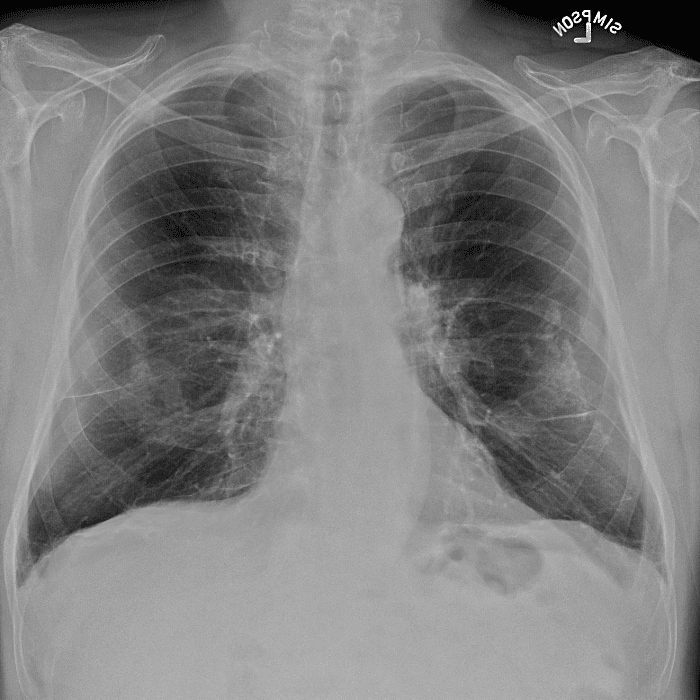

Practice Cases